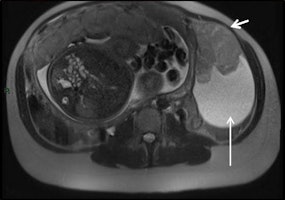

- Appendicitis: Ultrasound can be limited by the pregnant body habitus, especially in the later stages of gestation. MR should be performed in cases of inconclusive ultrasound.